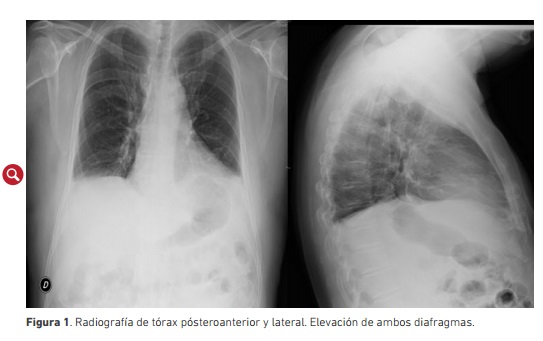

El hemograma, las pruebas de coagulación y los perfiles bioquímico renal y hepático eran normales, al igual que la medición de la aldolasa, las hormonas tiroideas, las inmunoglobulinas y el proteinograma. La gasometría arterial basal (con el paciente sentado) mostró alcalosis respiratoria (pH 7,50; presión arterial de dióxido de carbono 32 mm/Hg, presión arterial de oxígeno 82 mm/Hg, bicarbonato 25 y saturación arterial de oxígeno 98 % ). En la radiografía de tórax se encontró elevación de ambos diafragmas, principalmente del izquierdo (figura 1).

La radiografía y la tomografía axial computadorizada tóraco-abdominal también evidencian elevación de ambos hemidiafragmas, además de atelectasias basales bilaterales, sin infiltrados neumónicos residuales, ni defectos de repleción en las arterias pulmonares y ramas principales de tórax, y la radioscopia pueden evidenciar la reducción de volumen en las bases pulmonar como en el presente caso. La radioscopia puede ser negativa en bipedestación y mostrar la parálisis diafragmática cuando el paciente está en decúbito supino (6).